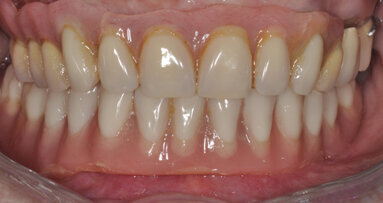

Lo scopo di questo articolo è presentare una alternativa terapeutica al rialzo di seno mascellare nei casi in cui si verifichi una estesa pneumatizzazione dei seni mascellari nella zona del primo premolare.

Nelle riabilitazioni implanto-protesiche del mascellare atrofico esistono delle alternative alla chirurgia di elevazione del seno mascellare che devono ...